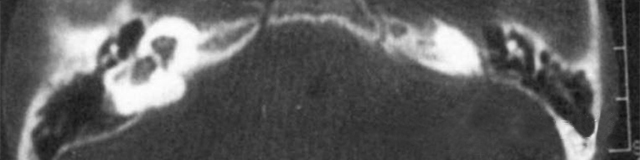

主要根據聽力學表現和影像學檢查。通過高分辨CT可看到耳蝸畸形。內耳MRI顯示膜迷路內水充盈,耳蝸扁平,耳蝸第二圈與頂圈間隔缺損,以及半規管、前庭的畸形。

先天性耳蝸畸形伴前庭和外半規管發育不良